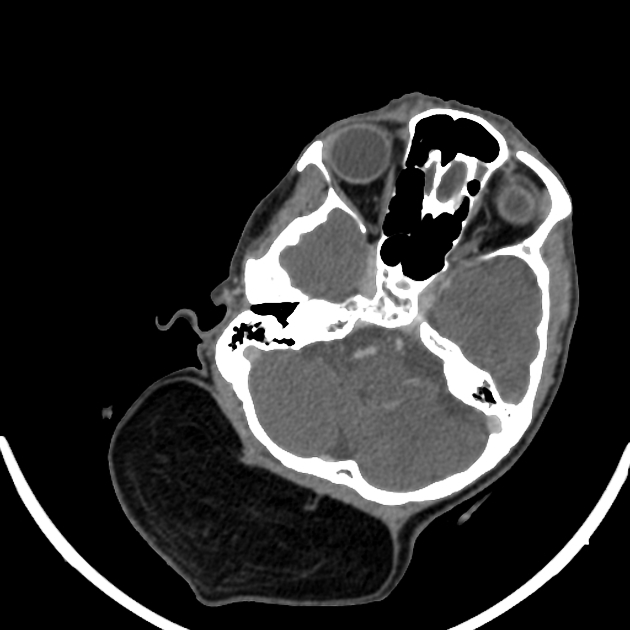

Компьютерная томография не является базовым исследованием для диагностики липомы, потому что не позволяет достоверно отличить доброкачественное жировое образование от атипичной липомы или липосаркомы при отсутствии выраженных плотностных изменений и специфических признаков васкуляризации. Липома представляет собой доброкачественную опухоль, состоящую из зрелой жировой ткани, которая может располагаться как поверхностно, так и в глубине мягких тканей. Базовым диагностическим исследованием является магнитно-резонансная томография с использованием режима подавления сигнала от жира. Оданко КТ выявляет следующие анатомические признаки:

В нативном режиме определяется гиподенсивное образование с плотностью, характерной для жировой ткани, с ровными и чёткими контурами.

В режиме сканирования мягких тканей визуализируется равномерная структура липомы без признаков кальцификации или плотных включений.

В артериальной фазе контрастирования отсутствует накопление контраста в области липомы, что подтверждает отсутствие активной васкуляризации.

В венозной фазе определяется стабильность плотности липомы без усиления, характерного для злокачественных образований.

В высокоразрешающем режиме уточняются размеры, границы и локализация липомы относительно окружающих тканей.

В режиме трёхмерной реконструкции детально отображается пространственное положение липомы и её отношение к соседним структурам.